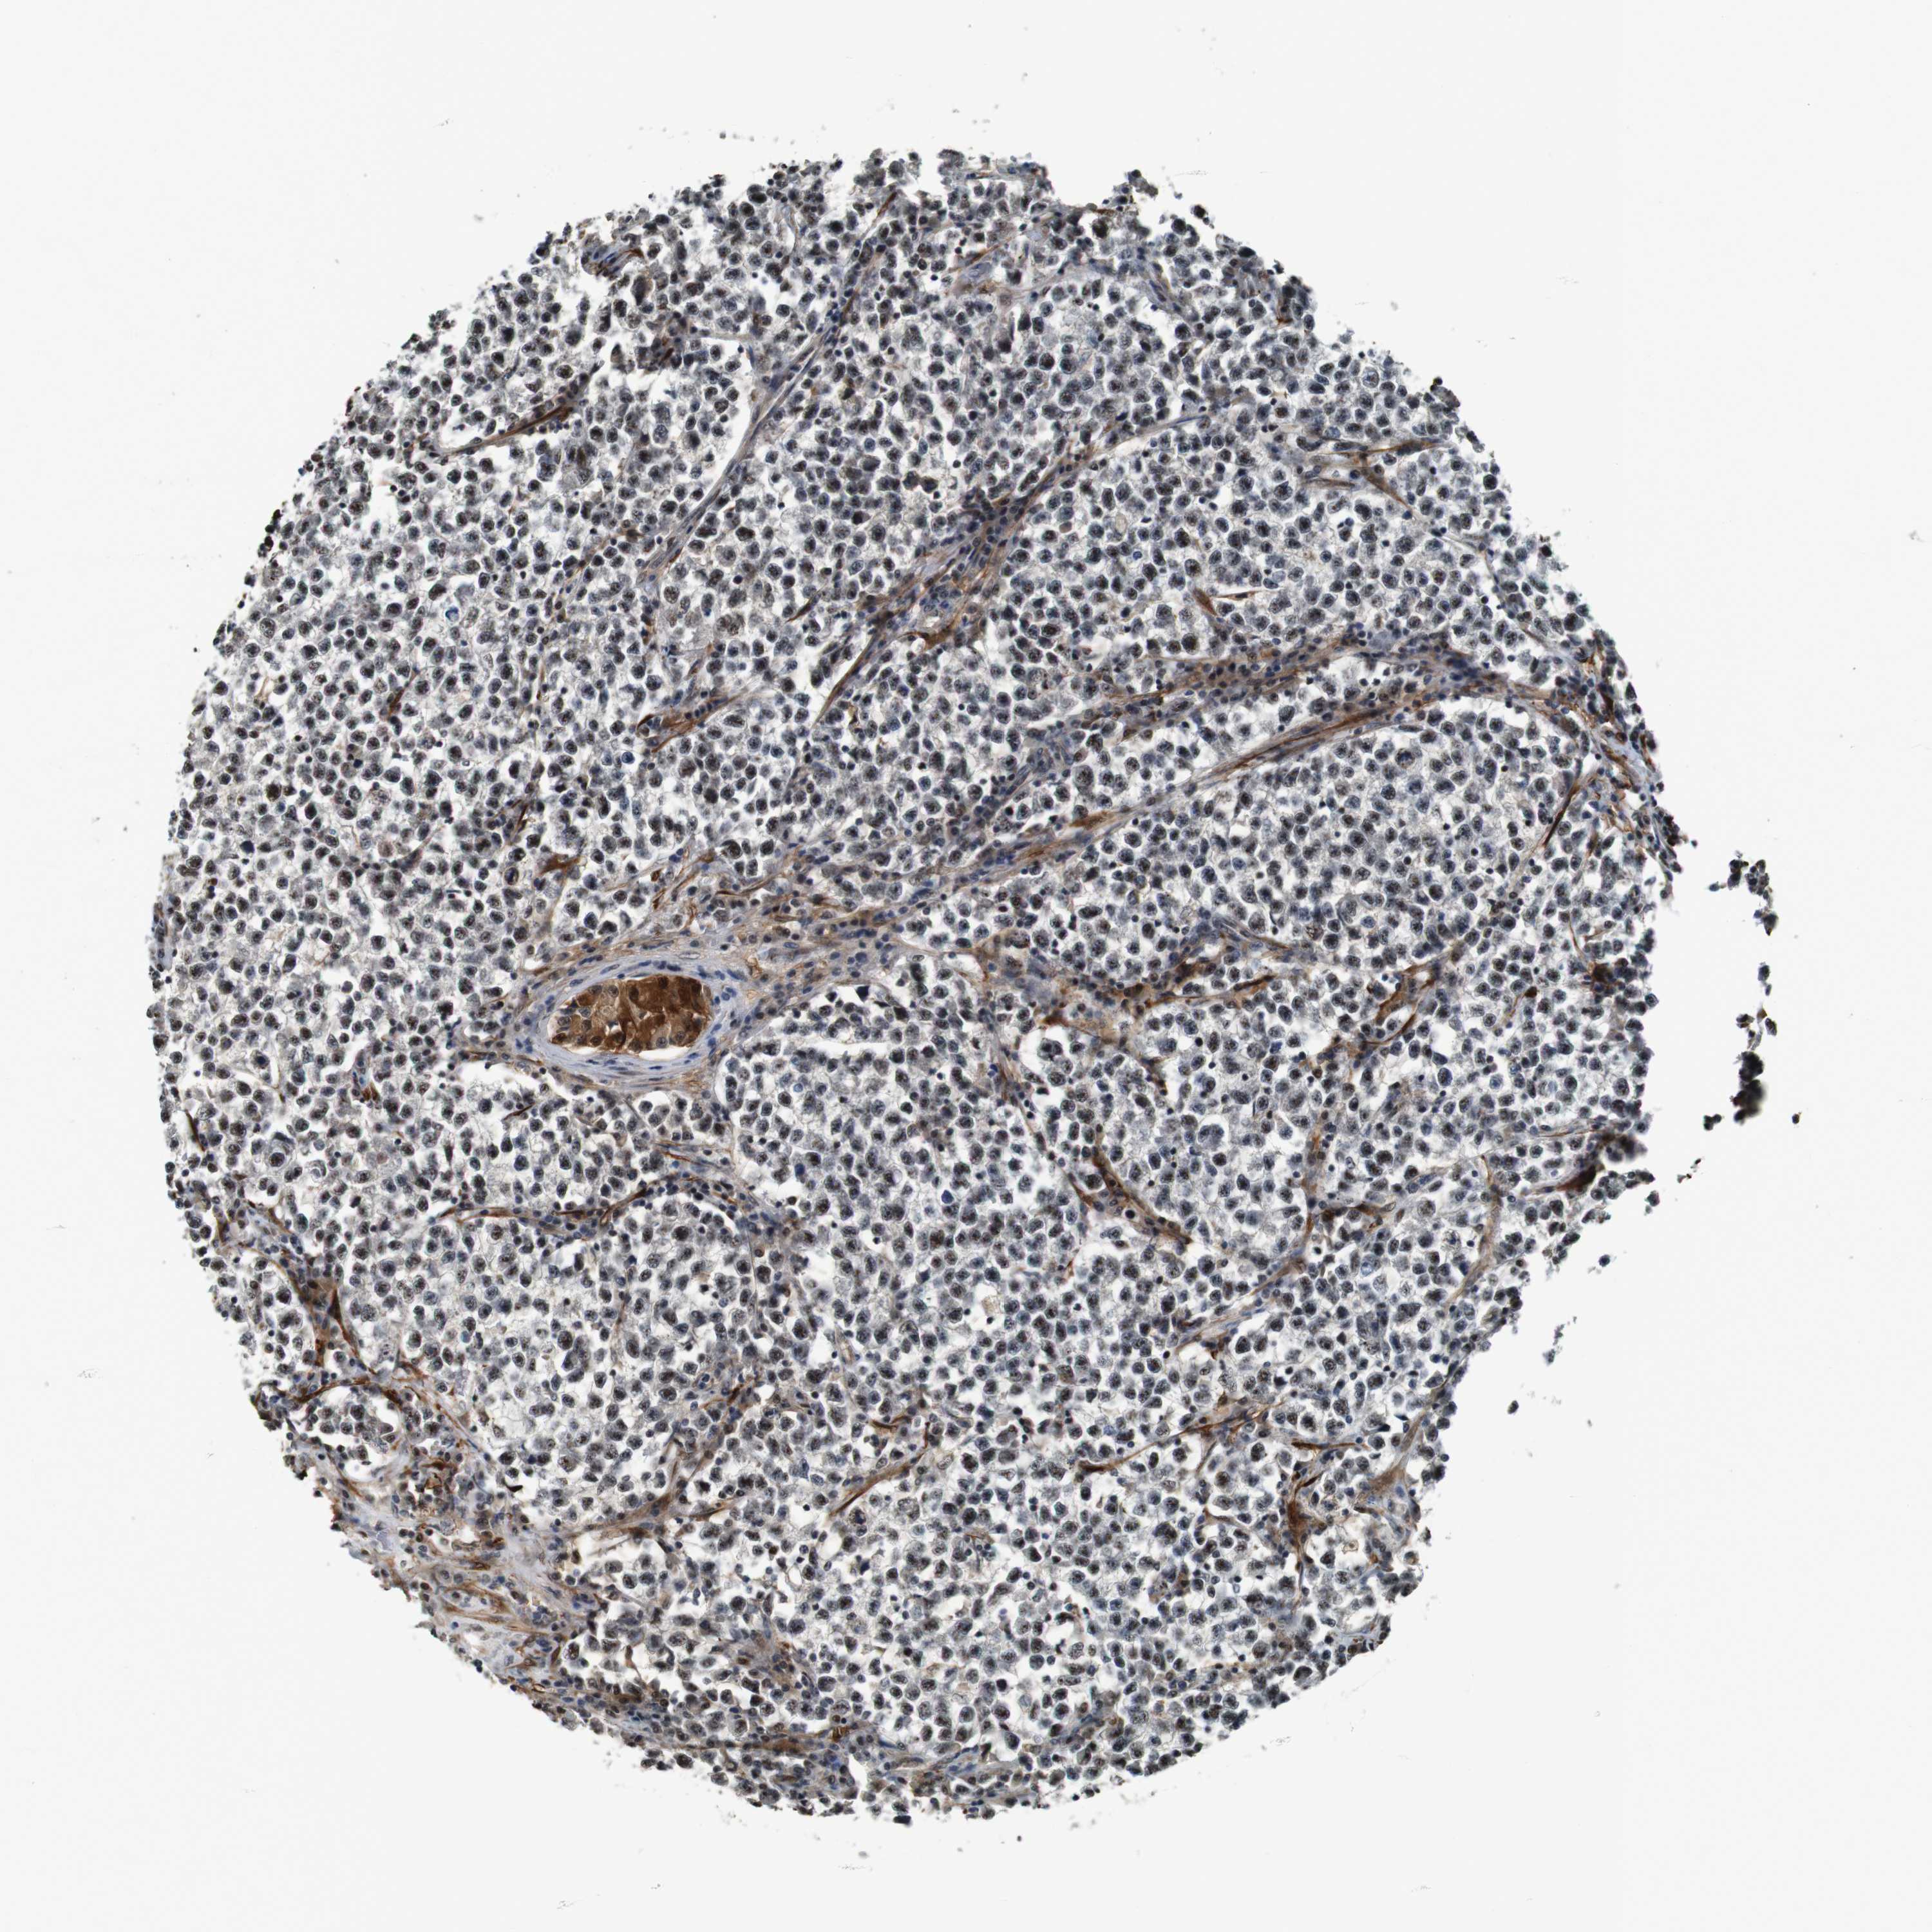

TESTIS CANCER - Protein expressioni

A mouse-over function shows sample information and annotation data. Click on an image to view it in a full screen mode. Samples can be filtered based on level of antibody staining by selecting one or several of the following categories: high, medium, low and not detected. The assay and annotation is described here.

Note that samples used for immunohistochemistry by the Human Protein Atlas do not correspond to samples in the TCGA dataset.

Antibody stainingi

Antibody staining in the annotated cell types in the current human tissue is reported as not detected, low, medium, or high, based on conventional immunohistochemistry profiling in selected tissues. This score is based on the combination of the staining intensity and fraction of stained cells.

Each image is clickable and will lead to virtual microscopy that enables deeper exploration of all samples and also displays staining intensity scores, fraction scores and subcellular localization as well as patient and tissue information for each sample.

Antibody HPA014179

Antibody CAB025128

Staining

High

Medium

Low

Not detected

Intensity

Strong

Moderate

Weak

Negative

Quantity

>75%

75%-25%

<25%

None

Location

Nuclear

Cytoplasmic/membranous

Cytoplasmic/membranous,nuclear

Carcinoma, Embryonal, NOS

Seminoma, NOS